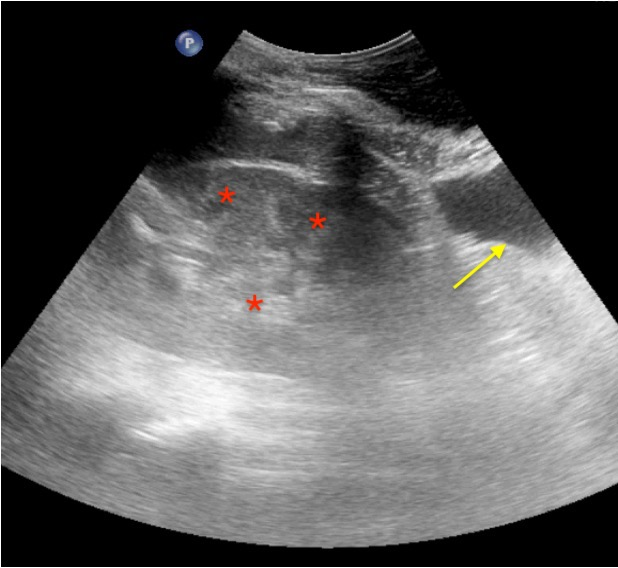

Real Images

Pneumothorax